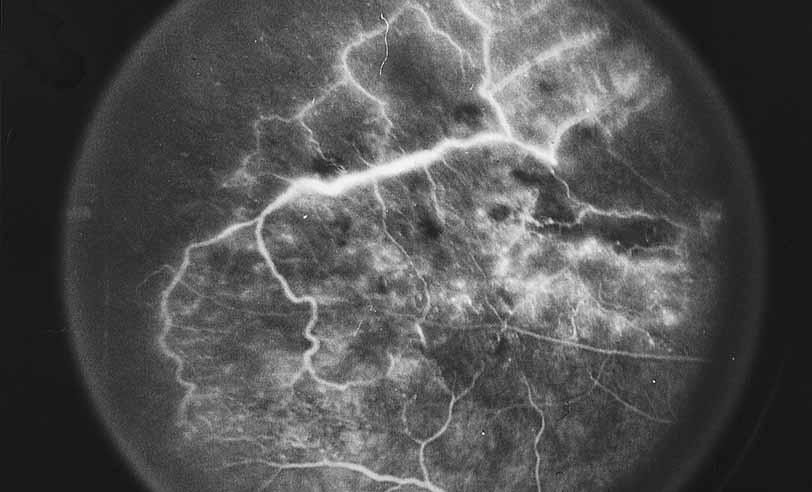

A third instance in which fluorescein angiography concentrating on the optic nerve may be helpful is in eyes with vascular engorgement of the optic nerve, especially with media opacities. Fluorescein angiography may help the clinician distinguish abnormally leaking capillaries from neovascularization. In acute multifocal hemorrhagic retinal vasculitis, optic nerve involvement is common in the early stages of the disease, 47 with optic nerve disc neovascularization seen later (see Figs. 10, 11, 12, and 13). Another fluorescein angiographic clue to the distinction between optic disc vessel engorgement and true neovascularization is the presence of associated large zones of retinal capillary nonperfusion such as those seen in sarcoidosis (see Figs. 14 and 15),34–40 acute multifocal hemorrhagic retinal vasculitis (see Figs. 10 and 11),47 or Eale disease (see Figs. 16 and 17).48–52

Fig. 10 Acute multifocal hemorrhagic retinal vasculitis. A middle-aged man presented with the picture of multiple branch vein obstructions and low-grade intraocular inflammation.

Fig. 11 Acute multifocal hemorrhagic retinal vasculitis. Fluorescein angiogram confirms the presence of associated retinal capillary non-perfusion without neovascularization at the onset of the disease.

Fig. 12 Acute multifocal hemorrhagic retinal vasculitis. The patient later developed disk neovascularization with vitreous hemorrhage. Note the areas of neovascular leakage from the optic nerve.

Fig. 13 Acute multifocal hemorrhagic retinal vasculitis. The patient underwent scatter laser photocoagulation to the zones of retinal capillary nonperfusion, which resulted in regression of the neovascularization.